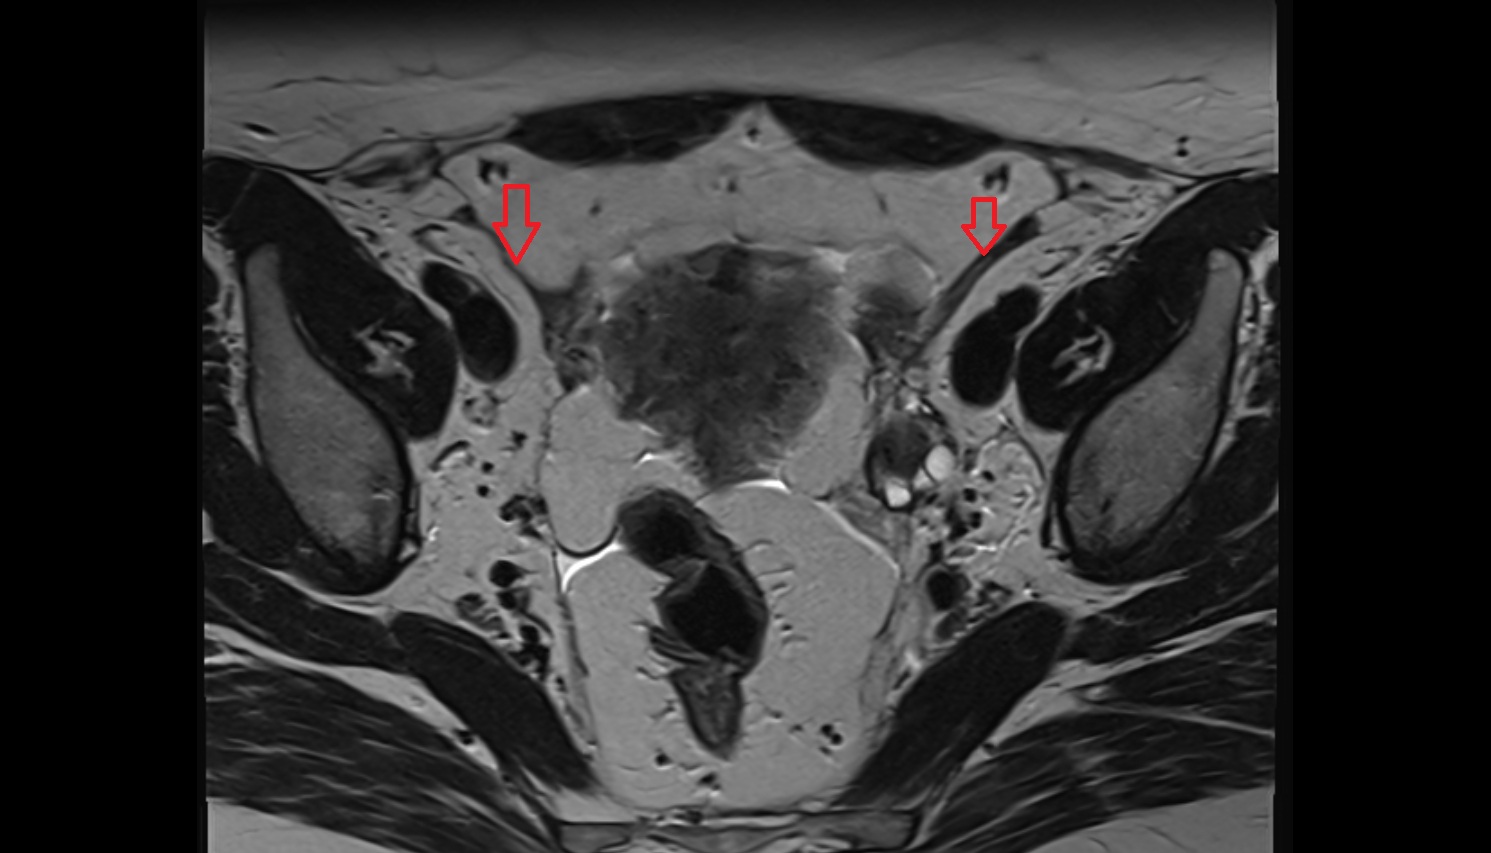

- Intermediate lacunar external iliac lymph nodes

- External iliac lymph nodes

- Obturator lymph nodes